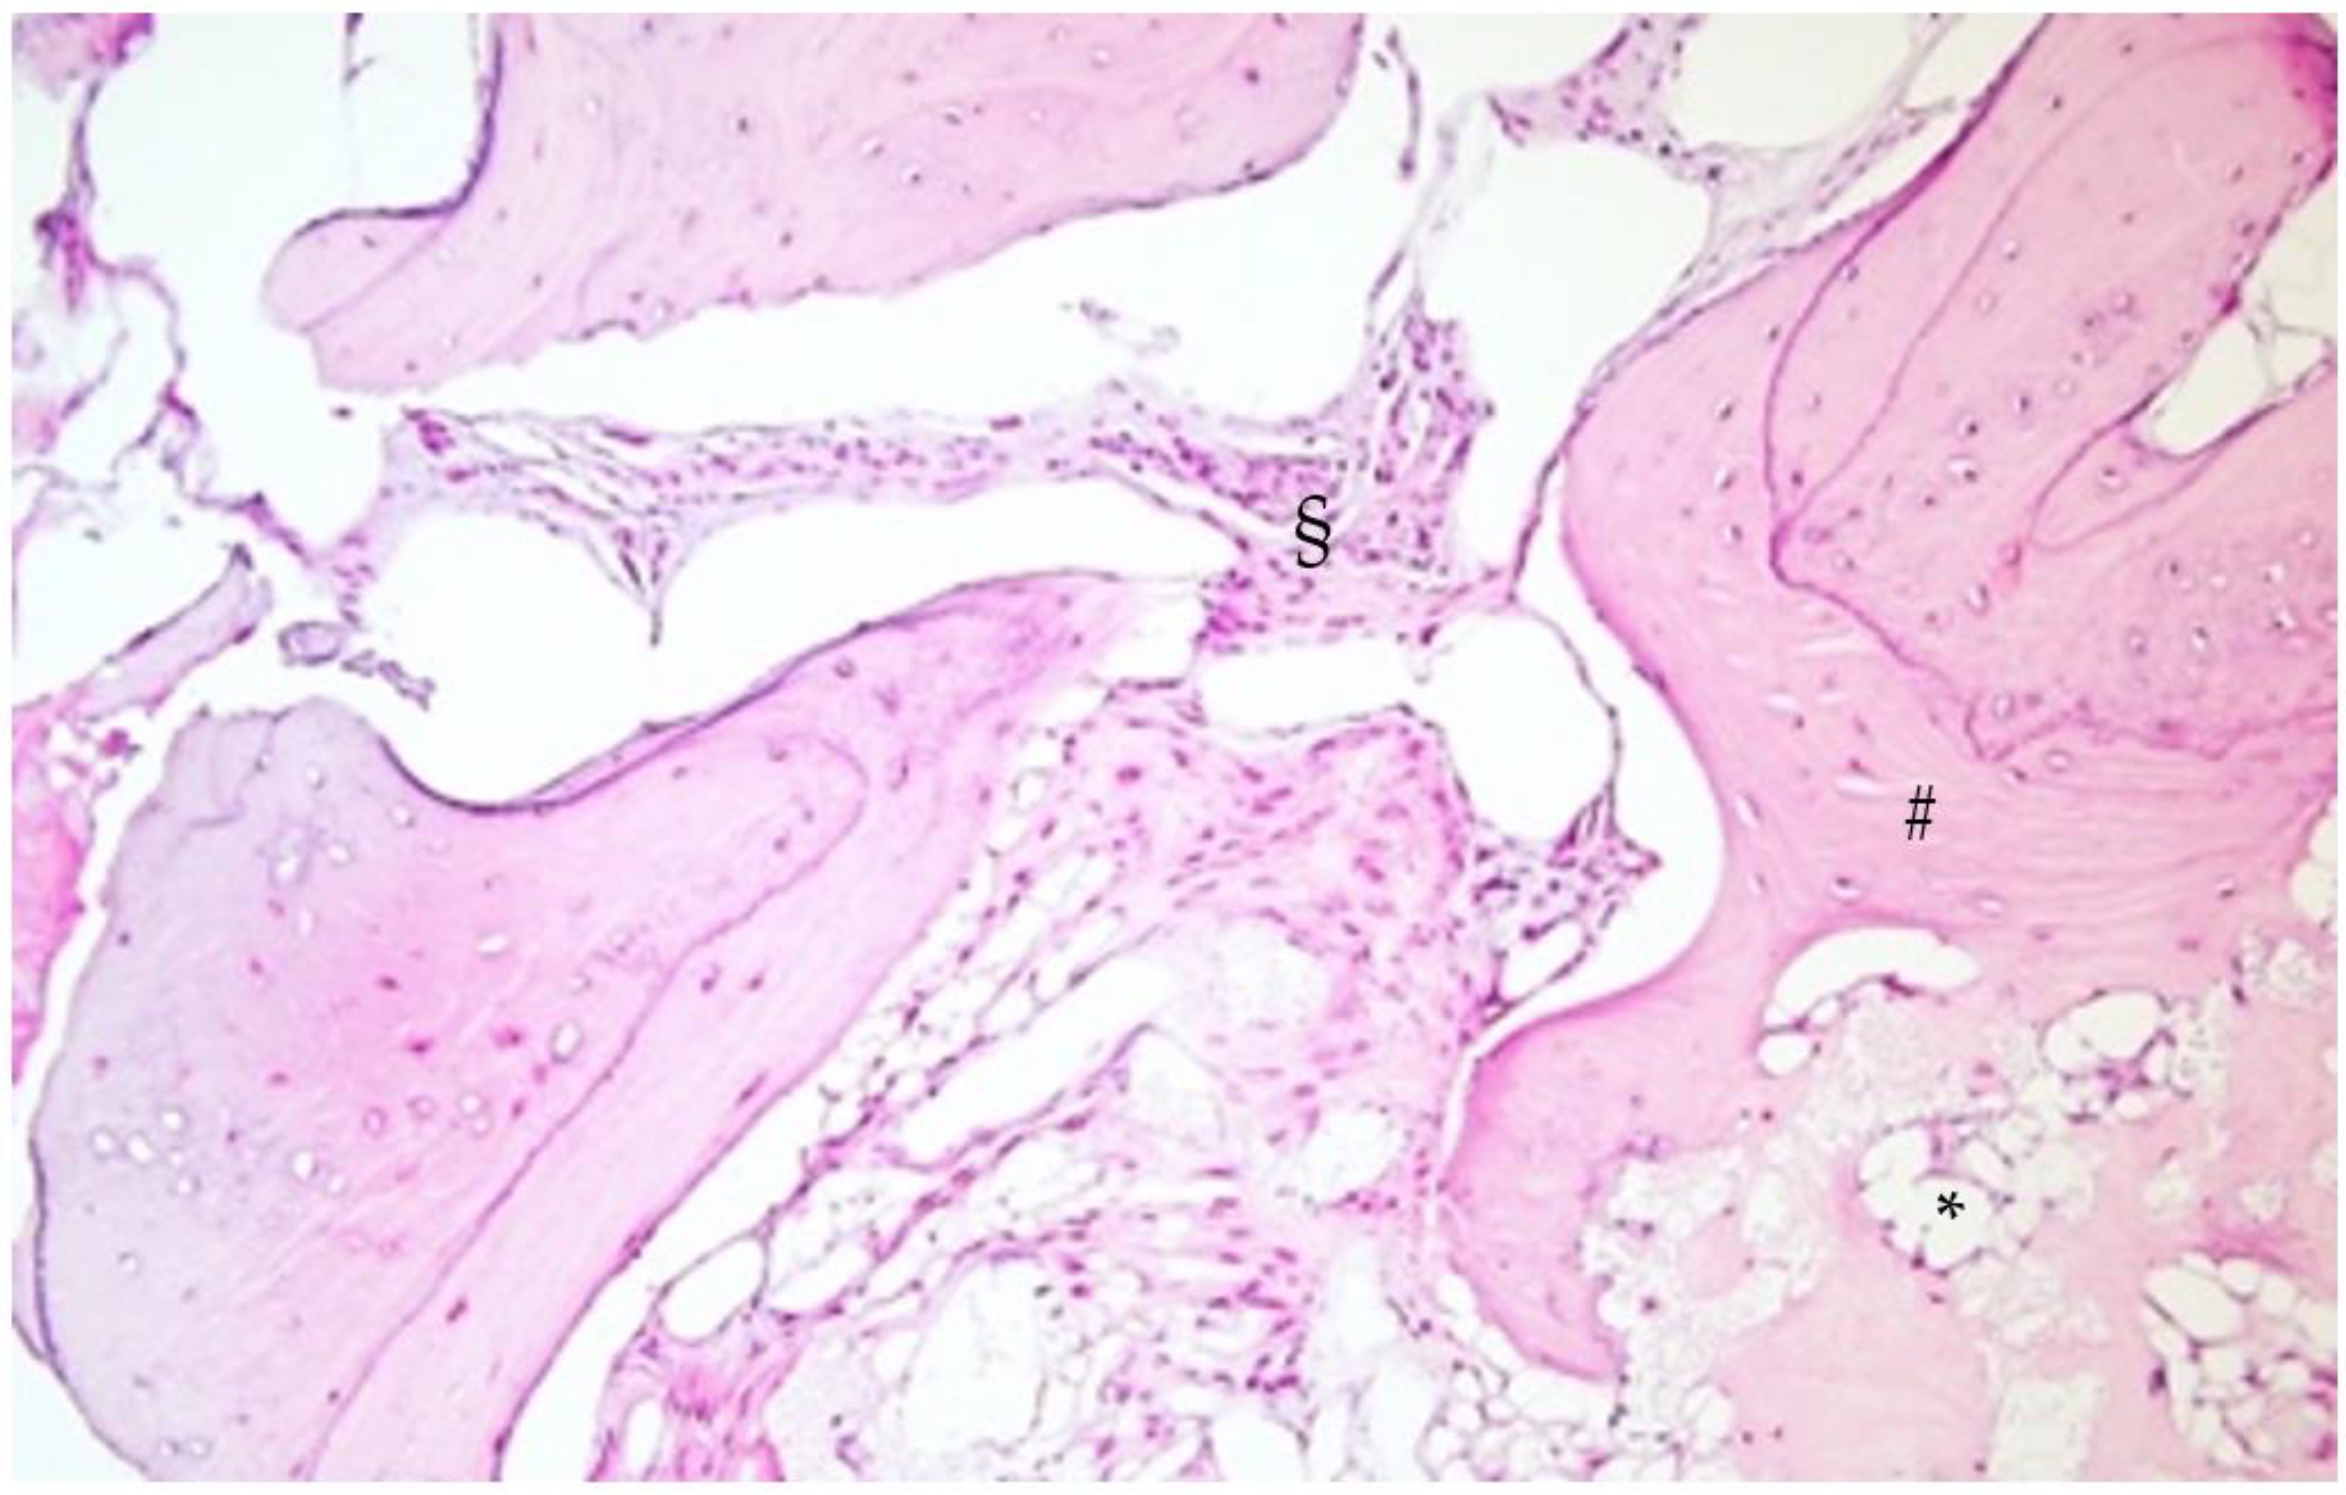

2.3. Histological Analysis